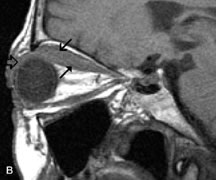

Intraorbital and intracranial optic nerve sheath meningiomas are usually isointense to cortical gray matter on Tl-weighted images and remain isointense on proton density studies (Fig. 15). Gd-DTPA is useful in delineating the intracranial extension of optic nerve meningiomas.7,47 The hyperostosis of bone and calcification associated with meningiomas are not demonstrated as well on MRI studies as on CT scans.20,37 Gd-DTPA–enhanced MRI also appears promising in the study of the permeability of the blood–brain barrier in selected optic neuropathies.22,48 MRI may reveal an enlarged optic nerve and some degree of contrast enhancement in cases of optic neuritis.49

Fig. 15. A. T1- and (B) T2-weighted MR scans demonstrate a mass causing fusiform enlargement of the optic nerve sheath complex. The peripheral portion of the mass, representing the meningioma, is isointense to brain on the T1-weighted scan and notably hypointense on the T2-weighted scan. The central portion of the mass, representing an edematous optic nerve, is very hyperintense on the T2-weighted scan (arrow), C and D. Postcontra fat-suppressed T1-weighted scans demonstrate intense peripheral enhancement of the meningioma surrounding the central nonenhancing optic nerve (arrow). Also note the enhancing Intracranial “dural tail” (double arrow).